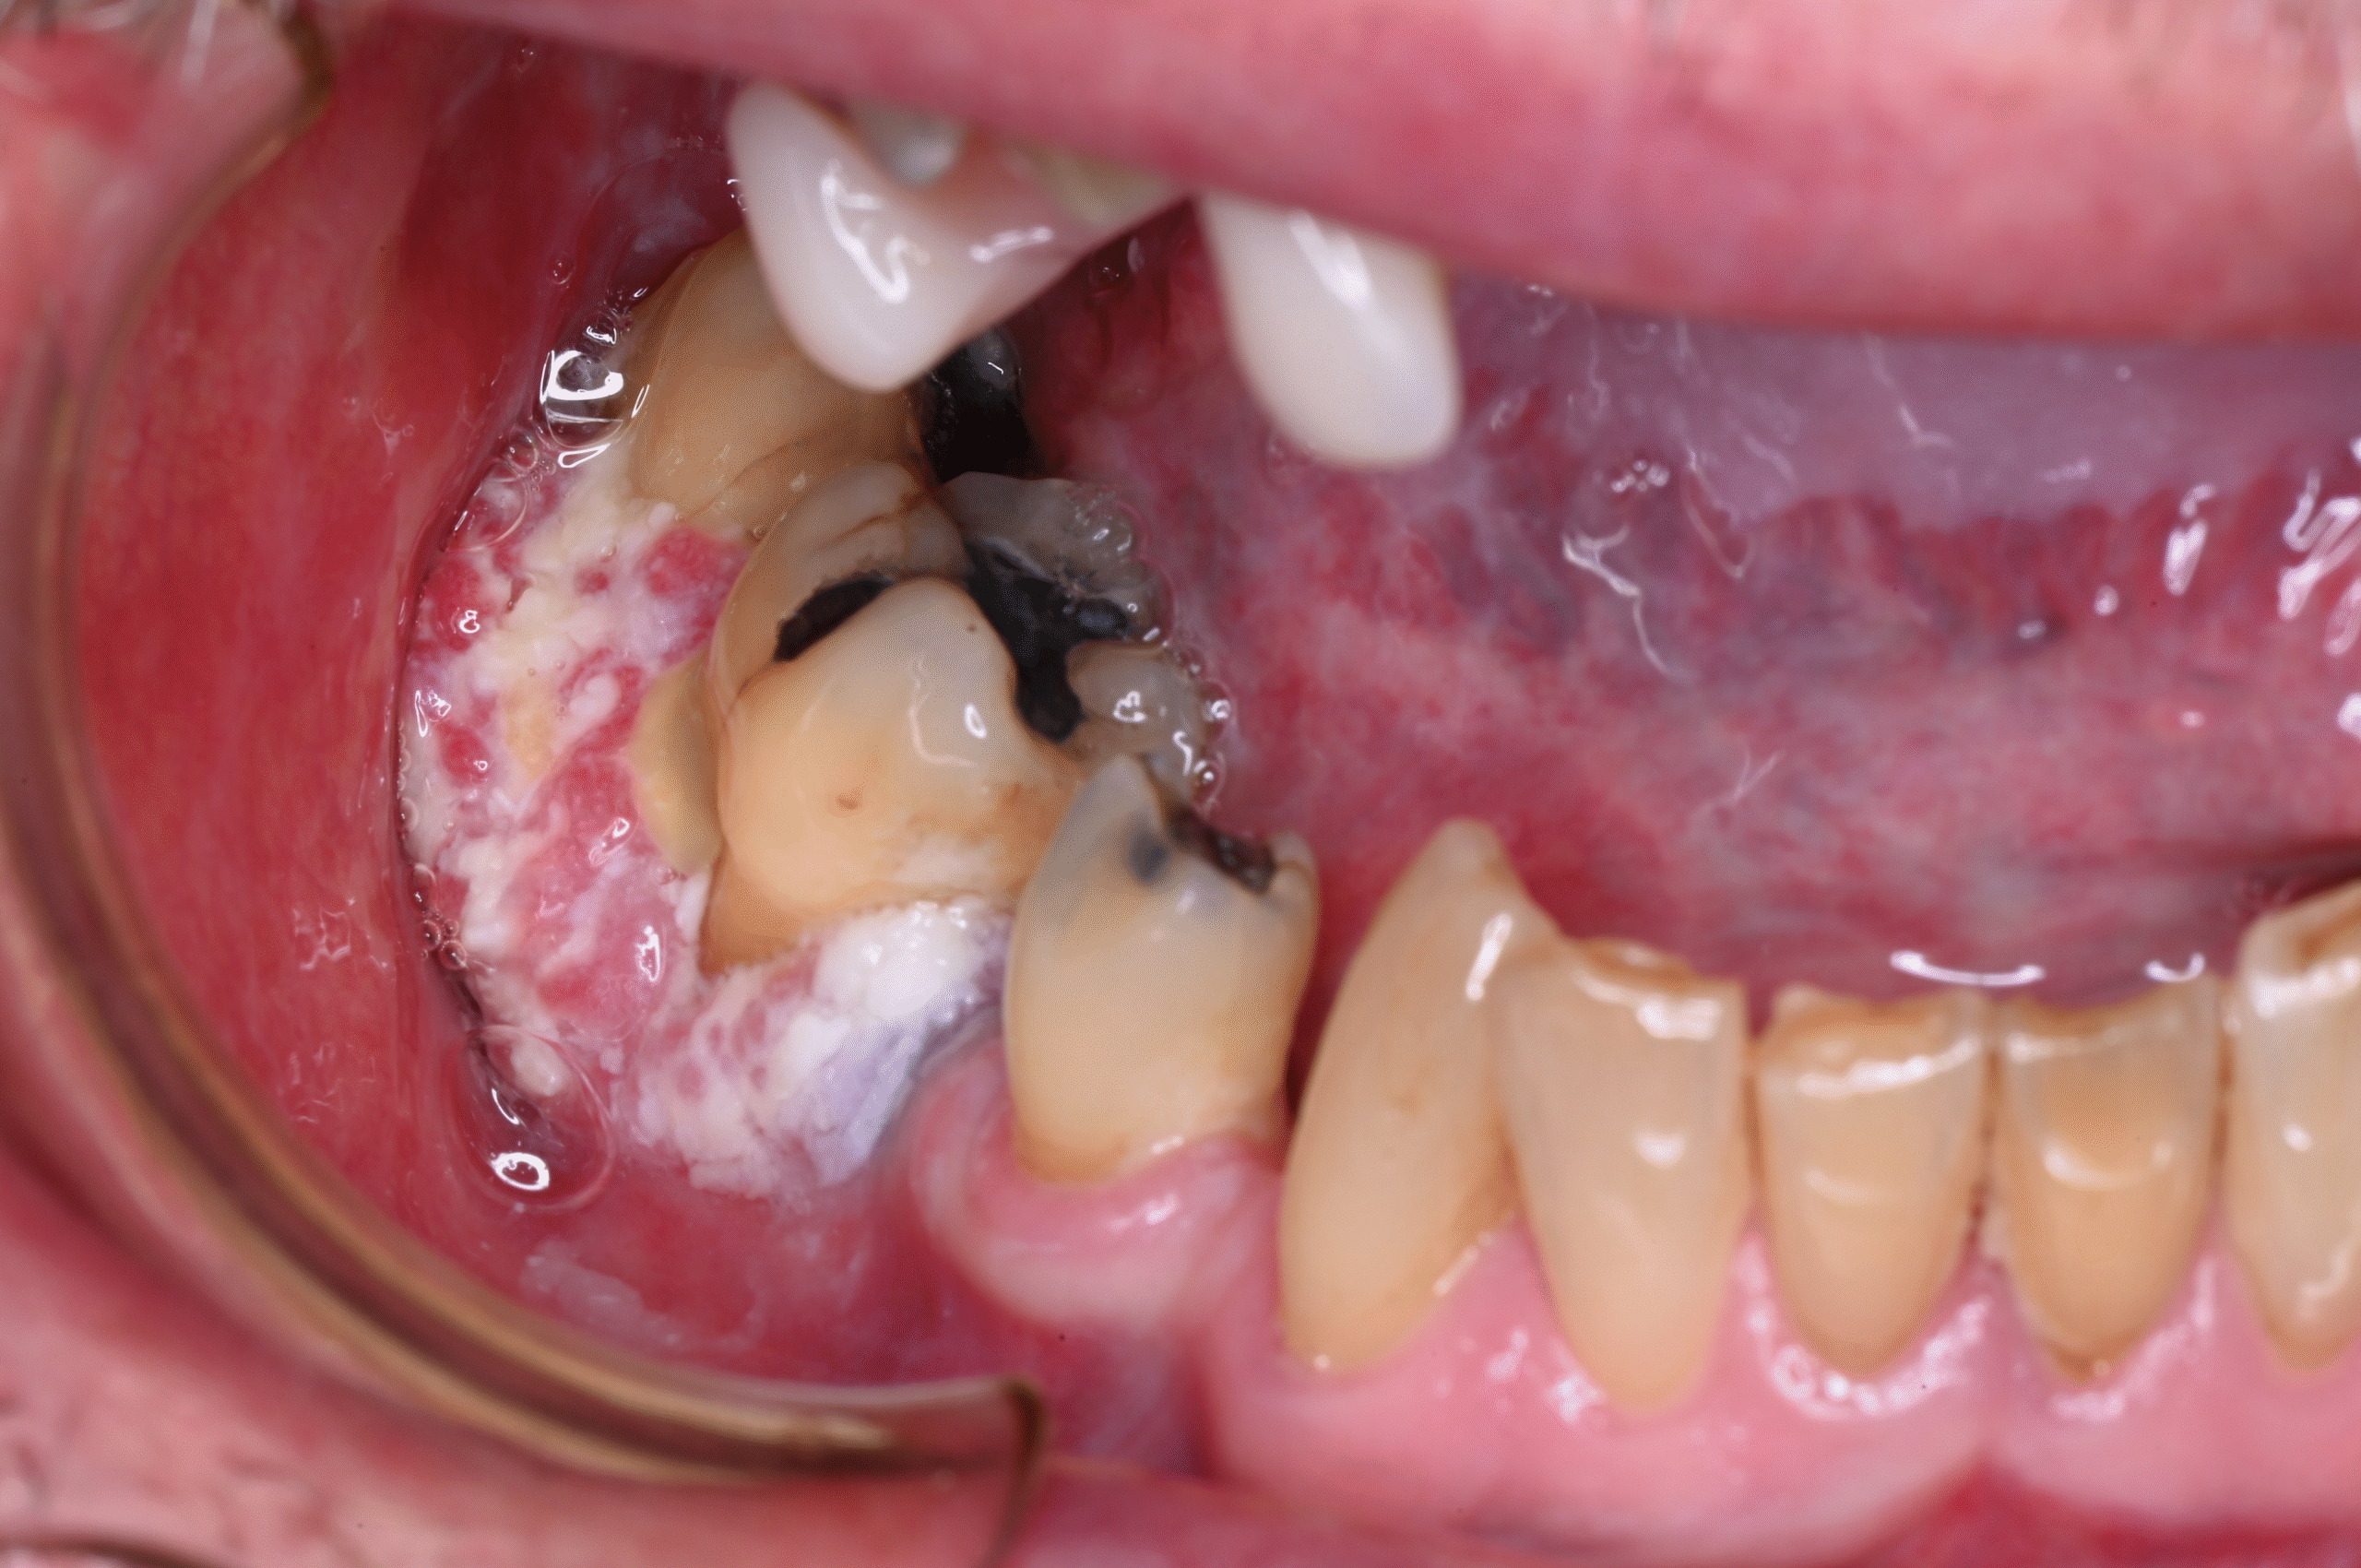

“I will discuss the widely ranging clinical presentation of mouth cancer, showing some case study examples and taking delegates through the assessment process from start to finish. As part of this, we will cover mouth cancer risk factors and their elimination, as well as the importance of detecting mouth cancer when the tumour is still small. I will also offer my usual quiz, allowing delegates to self-assess their confidence in diagnosing mouth cancer in real-life situations.